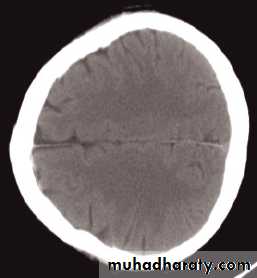

Computed tomography of the brain

• A routine CT examination of the brain involves making 20–30 axial sections.

• The axial plane is the routine projection but computer reconstructions can be made from the axial sections, which then provide images in the coronal or sagittal planes

• The window settings are selected for the brain and are also altered to show the bones

The cardinal signs of an abnormality on a CT scan are:

• Abnormal tissue density• Mass effect

• Enlargement of the ventricles.

Abnormal tissue density

• Abnormal tissue may be of higher or lower density than the normal surrounding brain.• High density is seen with recent haemorrhage, calcified lesions, and areas of contrast enhancement

• Low density is usually due to neoplasms or infarcts, or to oedema, which commonly surrounds neoplasms, infarcts, haemorrhages and areas of inflammation.

Mass effect

• The lateral ventricles should be examined to see if they are displaced or compressed.• Shift of midline structures, such as the septum pellucidum , the third ventricle, or the pineal, is a common finding with intracranial masses.

Enlargement of ventricles

There are two basic mechanisms which cause the cerebral ventricles to enlarge:• Obstruction to the CSF pathway, either within the ventricular system (non-communicating hydrocephalus) or over the surface of the brain (communicating hydrocephalus)

• Secondary to atrophy of brain tissue